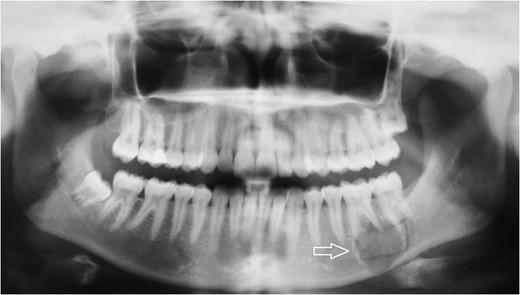

Follow-up panoramic X-ray imaging at 12 months after initial diagnosis showing no significant progression of the tumor lesion.